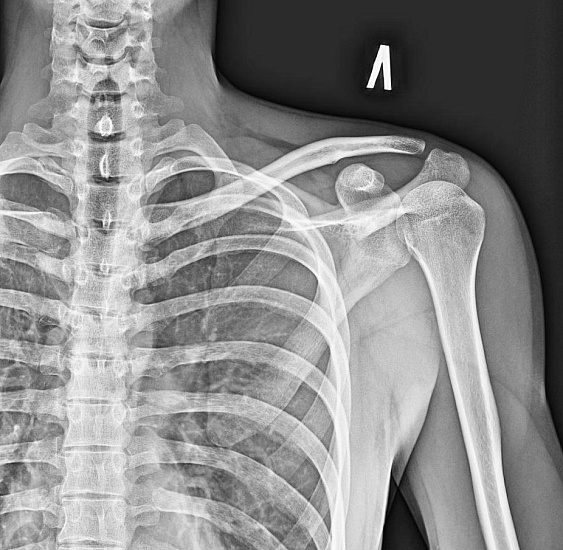

Рентгенография лопатки – важный метод прицельного исследования, который позволяет оценить состояние лопатки.

Диагностическая услуга выполняется в двух проекциях.

• травма лопатки в анамнезе (перелом, вывих);

• воспалительные процессы.

Рентген позволяет оценить наличие костно-травматической патологии лопатки.